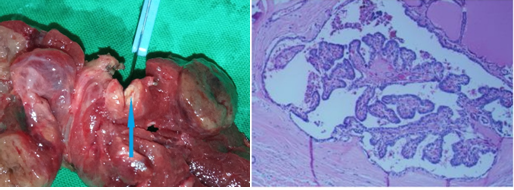

Green arrow — Right common carotid artery. Blue arrow — Right internal jugular vein. Purple arrow — Parathyroid adenoma. Yellow arrow — Right vagus nerve. Brown arrow — Trachea. Light brown arrow — Right recurrent laryngeal nerve (Courtesy Dr. V. Penopoulos)

Parathyroid adenoma. The cells demonstrate moderate pleomorphism, with centrally located round nuclei and clear/eosinophilic cytoplasm, without cellular atypia or mitotic activity (Courtesy Dr. V. Penopoulos)